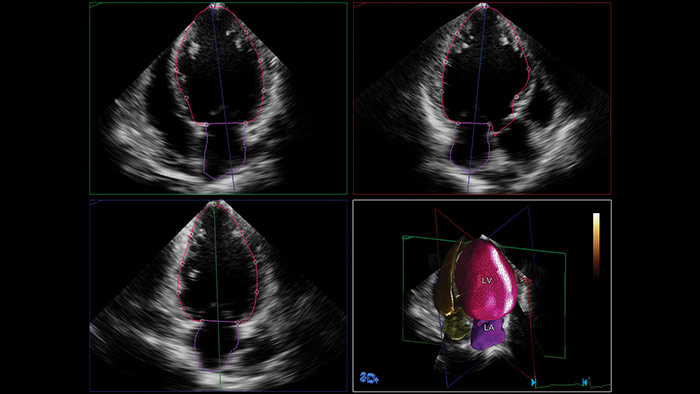

フィリップスのAnatomical Intelligence for Ultrasound(AIUS)は、高度な心臓のモデル化と実績のある定量化機能により、使いやすさ、高い再現性を実現。新しいレベルでの臨床情報の提供を可能にし、現代の医療現場が直面する経済的および臨床的課題に対応します。

AIUSは決まった手順を自動化し、ユーザーによる操作を最小限に抑えてコンピュータ主導解析を行う機能を備えています。臓器の構造を自動で認識し、解析を行うことでスクリーニング診断や計測の質を向上させ、心エコー検査をより迅速に、再現性高く実行することをサポートします。